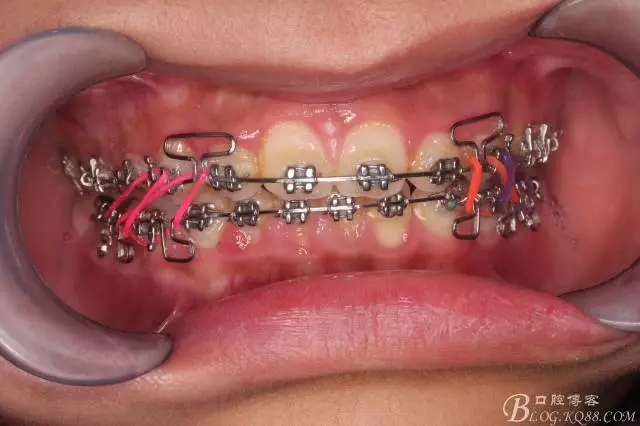

佩戴三個月的FR2, 效果奇佳!前牙基本達到淺覆蓋,淺覆合!接下來進入二期直絲弓固定正畸,排齊階段!

接下來盡管配合些雙側(cè)后牙對角牽引,咬合關系依,不盡人意。

下頜配合多曲方絲,三角牽引,調(diào)整咬合。